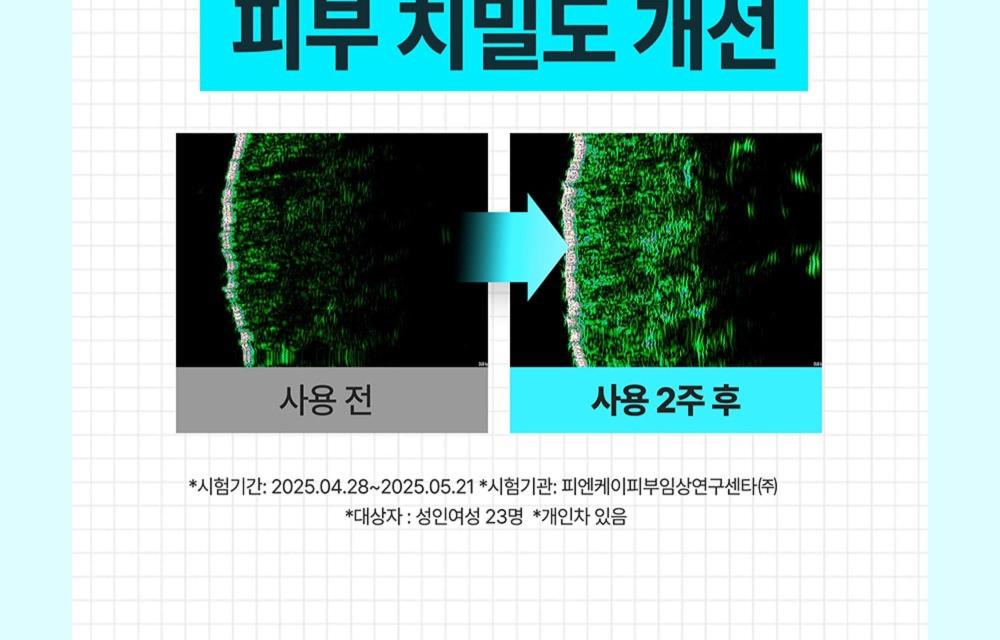

可見效果

- 僅 2 週使用,即可感受由內而外的緊緻水潤光澤肌膚。

- 「皮膚 plumping(豐盈)效果之人體適用試驗」。

- 物理性刺激造成受損肌膚的即時(暫時)內在屏障改善」。